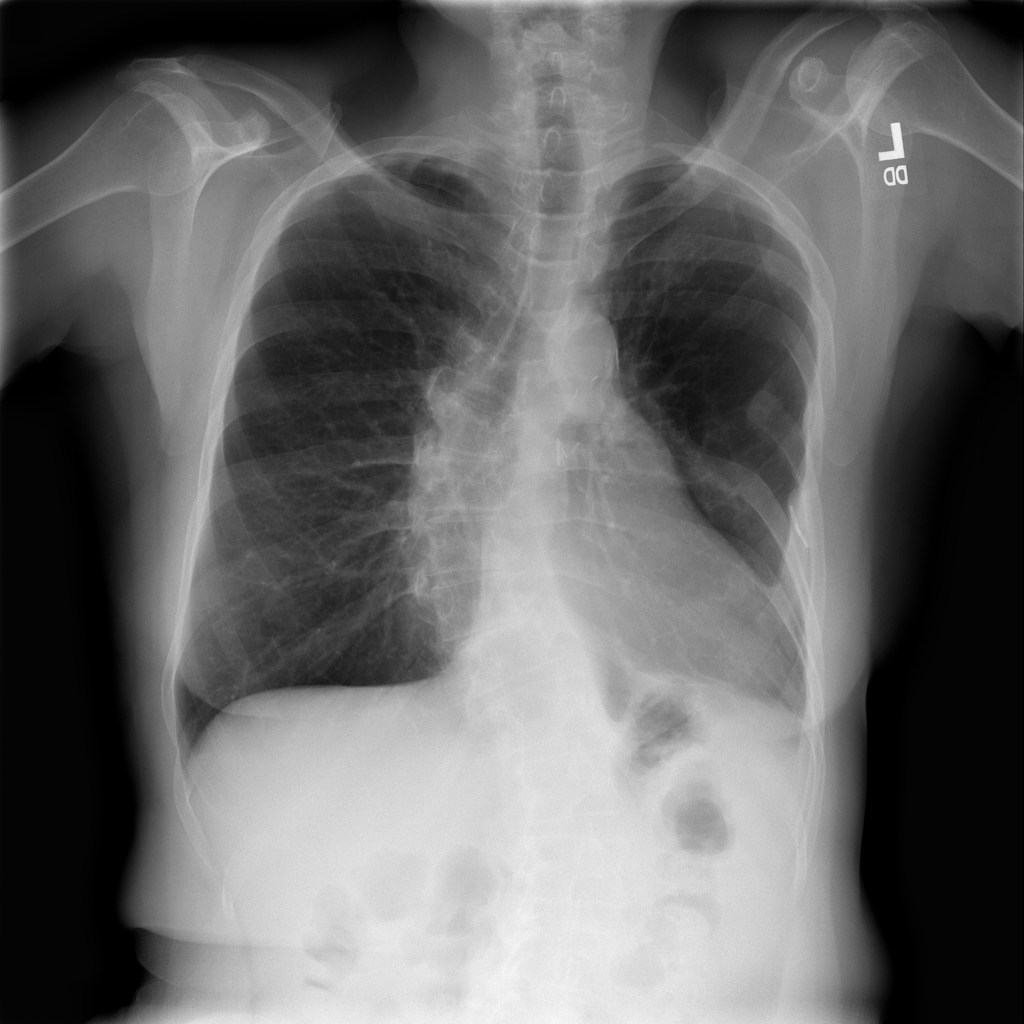

Mass

A mass is a larger focal opacity or lesion seen on the image. It is a descriptive finding that can have several causes and usually needs more imaging or clinical context to characterize.

PAT-D7A5 · IMG-000Mass

PAT-D7A5 · IMG-000

PA